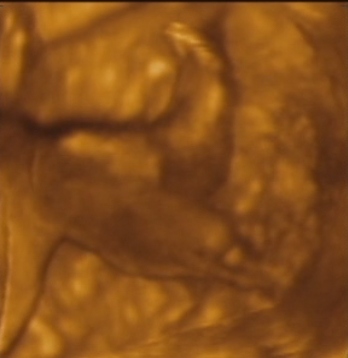

MPocAug12

MPocAug12 MBabuci1

MBabuci1 MBabuci2

MBabuci2

mosolygós kép...

mosolygós kép...